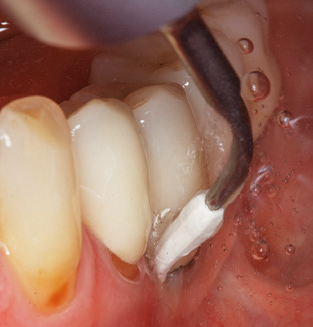

Unerlässlich für die UPT implantat prothetisch versorgter Patienten sind natürlich Arbeitsspitzen für die Reinigung von Implantatoberflächen. Der Implantatreinigungsaufsatz des hier verwendeten Systems zeichnet sich dabei durch eine spitz zulaufende sechskantige konische Form aus. Dieses Design erlaubt ein leichtes atraumatisches Eindringen in die periimplantäre Tasche und zeigt eine gute Reinigungsleistung (Abb. 7).

Nach der maschinellen Reinigung der Zahn und Implantatoberflächen erfolgt eine manuelle Instrumentierung der natürlichen Zahnoberflächen mit konventionellen Handinstrumenten. Bei der manuellen Reinigung ist insbesondere auf einen korrekten Anstellwinkel, eine ausreichende Schärfe, eine gute Abstützung und auf eine von apikal nach koronal gerichtete Arbeitsweise der Kürette zu achten. Zur Nachinstrumentierung der Implantatkonstruktionen sollten entweder Titan oder Carbonküretten verwendet werden (Abb. 8). Ergänzend zum Einsatz von Ultraschallgeräten können in der Erhaltungstherapie auch Pulverstrahlgeräte genutzt werden. Dabei ist jedoch zu berücksichtigen, dass diese Verfahren nicht zum Entfernen harter Beläge geeignet sind und daher die Verwendung von Hand oder Ultraschallinstrumenten nicht komplett ersetzen können. Abschließend erfolgt in jedem Fall eine mechanische Politur der zugänglichen Zahn und Implantatoberflächen mit Polierkelchen und Polierpasten (Abb. 9).